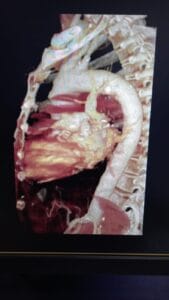

El Angio 3D es un procedimiento diagnóstico de última generación que utiliza equipos especializados como tomógrafos computarizados de alta tecnología...

La reconstrucción virtual es una técnica avanzada en radiología diagnóstica que aprovecha la tecnología de tomografía computarizada (TC) para crear...